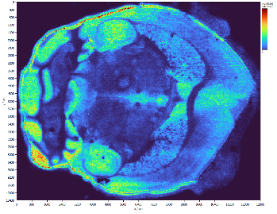

动物样本:鼠脑

空间分辨率:40μm

图片2.png

明场图